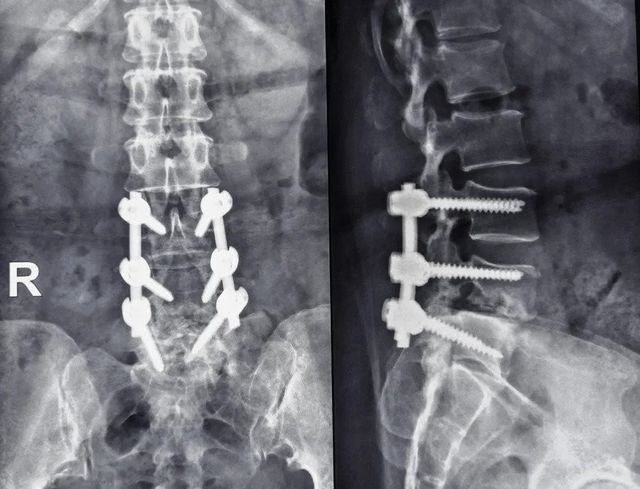

1734163664401.jpeg

23년 7월에 수술하며 철심까지 박은 경력이 드러남

여전히 예후가 좋지 않아 고통 받고 있었다고 함 ㅜㅜ